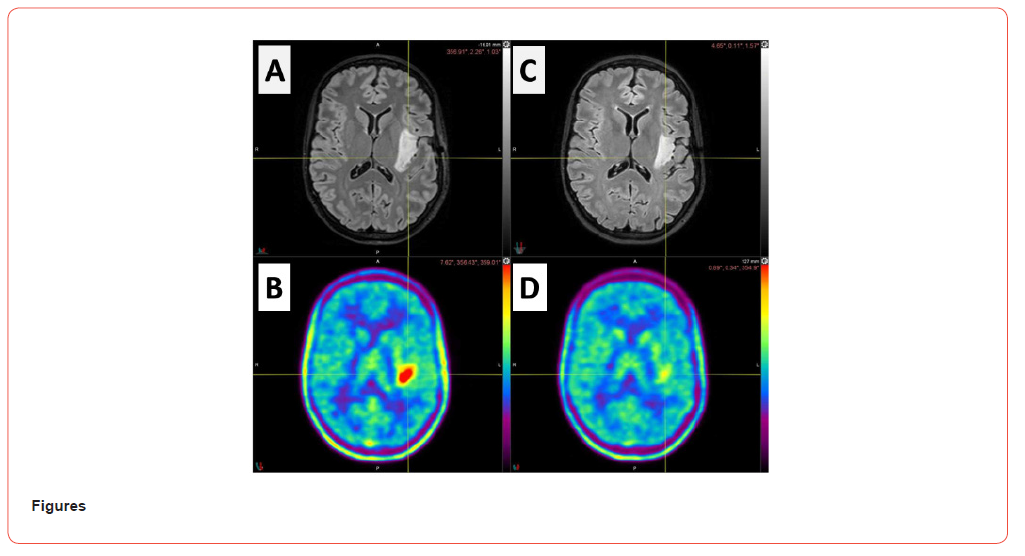

To delay radiotherapy, the adjuvant therapeutic option after subtotal resection of grade 2 diffuse astrocytoma, for this young patient, we opted for oral administration of the IDH inhibitor Vorasidenib (Servier) through a compassionate-use program. MRI and FET-PET seven weeks after surgery and prior to treatment with IDH inhibitor revealed a residual tumor in the FLAIR sequence (Figure 1A) with persistent metabolic activity at the superior border of the resection cavity (Figure 1B).

Eleven weeks after the initiation of IDH inhibitor treatment, FET-PET revealed an early, almost complete metabolic response of the residual glioma. After six months of IDH inhibitor therapy, MRI revealed a slight decrease in the FLAIR volume hyperintensity in the left lateral temporal lobe (from 16 cm3 to 12 cm3) (Figure 1C) whereas FET-PET confirmed a maintained metabolic response (Figure 1D). The IDH inhibitor dosage was reduced from 40 mg daily to 20 mg daily because of patient fatigue and an increase in hepatic transaminase levels as revealed by blood analyses. The patient-reported frequency of focal epileptic seizures improved with the use of Vorasidenib. FET-PET imaging appears to be useful for early assessment of the treatment response to IDH inhibitor for patients with residual IDH-mutated glioma.